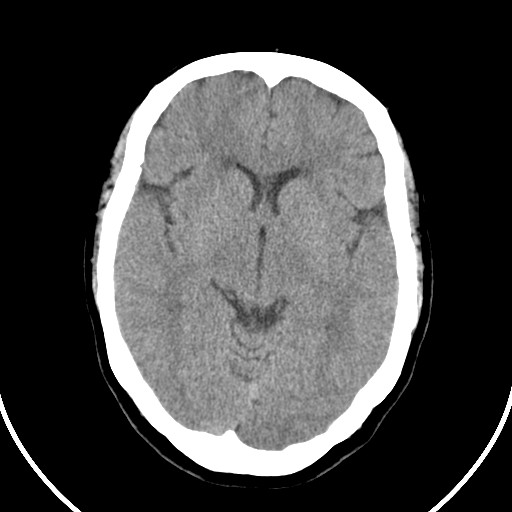

标题: CT21850:女,56岁,右中指淤肿,右手麻痹1天

女,56岁,右中指淤肿,右手麻痹1天

右侧侧脑室旁脑白质腔隙性脑梗死。

右侧基底节多发小梗塞

右基底结区腔梗

右侧基底节区腔隙性脑梗塞

右侧基底节多发腔梗!

双侧侧脑室额角旁对称性略低密度影,边缘模糊,无占位效应,考虑轻度脑白质稀疏症(病人有高血压吗).,右枕叶低密度影多为伪影,不放心薄扫一下.

考虑脑白质病。

考虑脑白质病

右枕叶条状低密度影不应该忽略可能极具意义